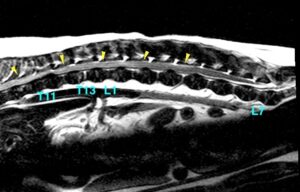

[胸部矢状断像、T2強調画像]

第11胸椎と第12胸椎の間で椎間板物質が飛び出し、脊髄が重度に圧迫されている(水色矢頭)

また第5胸椎から第4腰椎付近まで白くなっており(黄矢頭)浮腫や炎症のほかに出血、壊死、軟化などが疑われた。